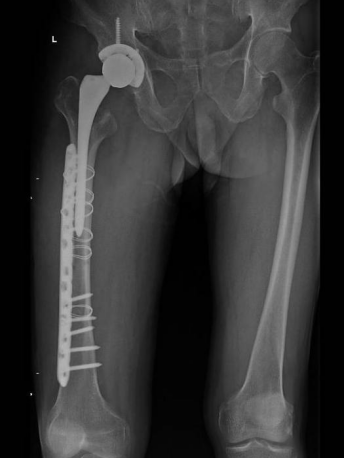

[ 老陶的术前影像(左)与术后影像(右) ]

一味地止痛也不是长久之计,于是老陶又换了一家医院,这次复查髋关节X光片发现右侧股骨颈已断裂。这家医院立即给老陶做右侧髋关节置换手术。手术中发现股骨颈肿瘤,做了肿瘤刮除,但手术中股骨大段劈裂,随即行钢板螺钉固定+钢丝辅助固定。

许宋锋主任初步分析:目前肿瘤仍有残余,右侧股骨劈裂,右腿比左腿长了2公分。唯一值得庆幸的是,癌细胞还没有大范围扩大。经过充分评估后,许宋锋主任建议老陶进行二次手术,扩大肿瘤切除范围,置换新的量身定制的假体。